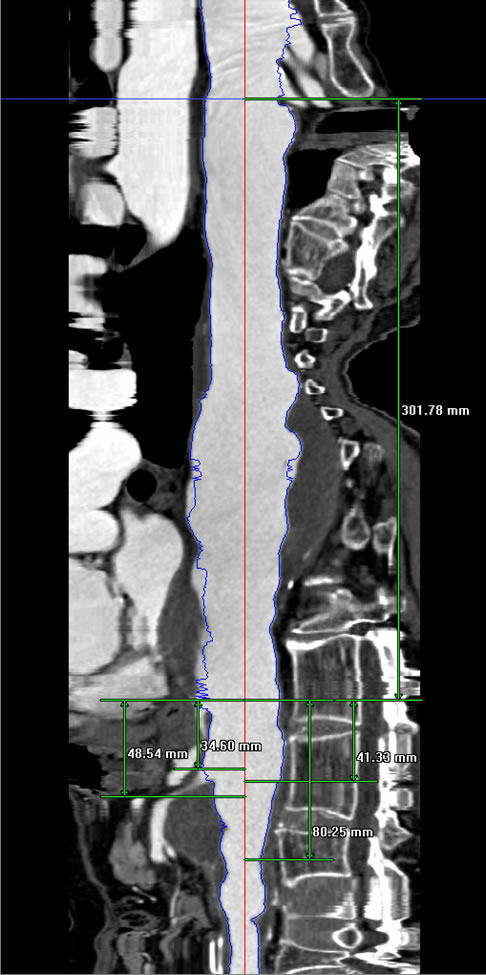

Planning

The operator needs to re-familiarize himself with the specific device design especially regarding the location of the fenestrations in relation to the edge of the graft material and to one another and also the predetermined access.

Bilateral common femoral arteries are exposed and access obtained on the side of delivery. The catheter is then directed to the ascending aorta and exchanged for a stiff guidewire (0.035 Amplatz or Lunderquist). A large bore (20-24F Check Flow) sheath is placed in the contralateral femoral vessel and multiply punctured with short 5F sheaths (Figure 3).

Once bilateral wire access has been obtained, the patient is heparinised. A straight angiography catheter is then positioned at the level of the diaphragm and angiography performed to delineate the visceral segment.

The device is then oriented ex vivo. The device is then advanced through the femoral artery to the level of the visceral segment and aligned with the appropriate branch arteries. Doing so may require multiple low-dose contrast injections.

It is important to also verify that the distal aspect of the device is above the aortic bifurcation. Once orientation of the proximal body has been confirmed, the top two stents are partially deployed. The device position is then adjusted as necessary in both the longitudinal and rotational planes. The sheath is then completely withdrawn to expand the stentgraft throughout its length. At this point the device is only partially expanded due to the presence of constraining wires. The next step entails cannulation of the fenestrations. The contralaterally placed wire and angiocath should be withdrawn at this point and the main body of the device recannulated. Using an appropriately angled catheter and flexible angled guide wire, at least two fenestrations and their corresponding arteries should be cannulated. With catheter access to the target artery the wire should be exchanged for a stiffer access wire (Rosen). An access sheath (7Fr Ansel) or guiding catheter (8Fr MPB) should then be advanced through the fenestration into the artery. This step should be repeated for at least two of the branch arteries before releasing the constraining wire.